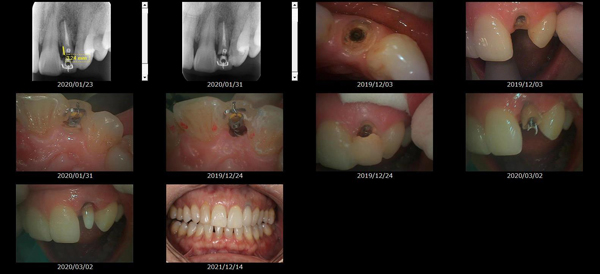

救歯MTM

虫歯が大きくて残せない歯、転倒などの事故により歯が根の深いとこで折れてしまったなどで、抜かざるを得ない歯を、骨の中に埋まっている健全な根を、骨の上に矯正的に引き上げることで、その歯を抜かず温存、救歯できる可能性のある治療方法です。

この特別な診療である救歯MTMは、以下のような特徴があります。

①健全な歯を、歯肉から見える位置にまで引き上げることで

根の治療の成功率を上げることが出来る。唾液には沢山の細菌がいます。唾液が入らない環境での根の治療を(神経の治療)を行うことで神経の治療、根の治療の成功率は格段と上がります。

②骨の上にある歯と土台で支える被せもの製作できる。

被せものを土台だけに頼ることなく、引き上げた健全な歯でも支えることで、歯への被せ物がしっかりと装着できるようになる。

③抜かずに歯を活かすことで、隣の歯を削るブリッジやインプラントにしないで済むことがある。

歯を矯正的に引き上げることで、その歯を救歯できるだけでなく、隣の歯を削るなどの侵襲を回避できる場合がある。

救歯治療と審美性の両立

当院では様々な治療の基礎に審美と機能の両立というテーマがあります。

リスク

- > 歯を矯正的に引き上げることで、骨の中の根の長さは短くなりますが、その短さでも安定するという診断をした場合のみ施術になります。 残せる歯、根の長さが短い場合は、この救歯MTMの治療対象とならない場合がございます。

- > 治療期間が数か月~1年に及ぶ場合がある。

- > 費用が自費診療 44,000円 ~ 66,000円

- > 救歯MTMは救歯BTAセラミックと併用治療が必要な場合があります。

症例